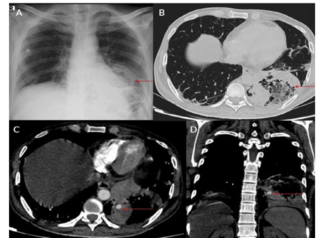

This study included COVID-19-positive patients who presented with massive hemorrhage who were referred to interventional radiology.